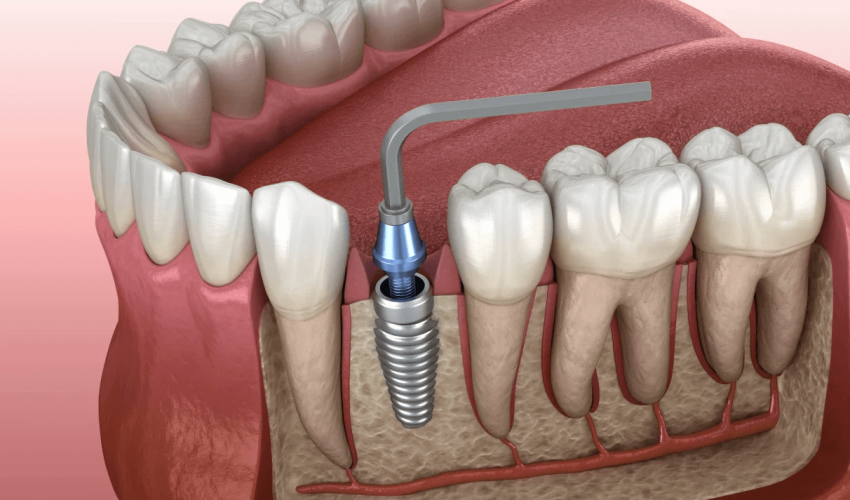

● Define immediate implant placement and its rationale, especially in esthetic and posterior zones

● Understand prosthetically driven, 3D implant positioning for esthetic success

● Identify correct drill entry points (palatal wall in anterior, furcation bone in molars)

● Recognize importance of atraumatic extraction, including root sectioning in molars

● Describe proper drill angulation (mesiodistal and buccolingual) and use of paralleling pins

● Understand drill sequence, including rationale for extending drilling depth 2 mm beyond implant length

- Fundamentals of Immediate Implant Placement in the Esthetic Zone + Initial Drilling of the Implant Site

- Continuation and Completion of Implant Site Drilling

- Selecting the Proper System for Immediate Implant Placement in the Esthetic Zone + Implant Insertion

- Post-Insertion Procedures: Choosing a Cover Screw or Healing Abutment + Ideal GBR in Immediate Implant Placement in the Esthetic Zone

- Unique Considerations for Immediate Implant Placement in the Posterior Region